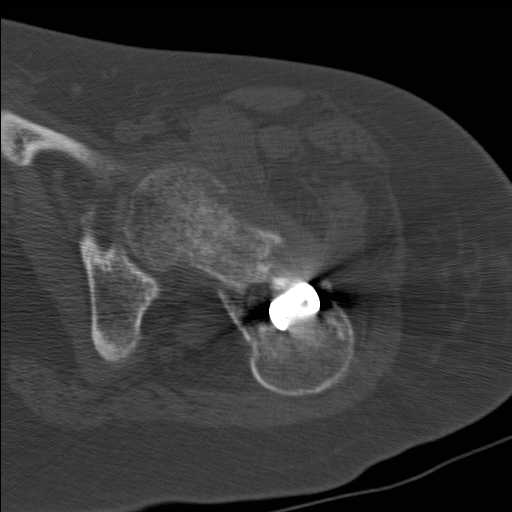

Добрый день уважаемые коллеги. Во такая ситуация. Девушка 19 лет травму получила в мае 2016г (изолированная травма, трансцервикальный перелом шейки левого бедра). Соматически здорова. Лечилась по месту жительства скелетным вытяжением в течении 1 месяца.

Затем переведена в наше учреждение. 18 июня выполнена операция, детали где , кто и как уточнять не имеет смысла( из протокола операции: выполнялась передняя артротомия, репозиция под визуальным контролем) . Учитывая характер выполненного остеосинтеза, после операции постельный режим 6 недель. Снимки в хронологии все выкладываю. КТ контроль сделан 2.09.16. для оценки состояния головки бедра. Помогите, определиться с дальнейшей тактикой.

согласен с Александром Николаевичем, надо пытаться сохранить сустав (в т.ч. его страдающее кровоснабжение. Судя по КТ Сохраняется ретроверсия шейки бедра. Вероятны трудности с репозицией последней. Для создания правильного направления шеечных винтов (Винта) возможно придется делать вальгусно-антекурвационную межвертельную остетомию, тем самым произвести разгибание в т/бедренном суставе проксимального отломка. И ретроверсия станет в большей степени вальгусом. То есть точка входа для гвоздя должна быть кзади от торчащей части прорезавшегося клинка со всеми вытекающими перемещениями проксимальной части.